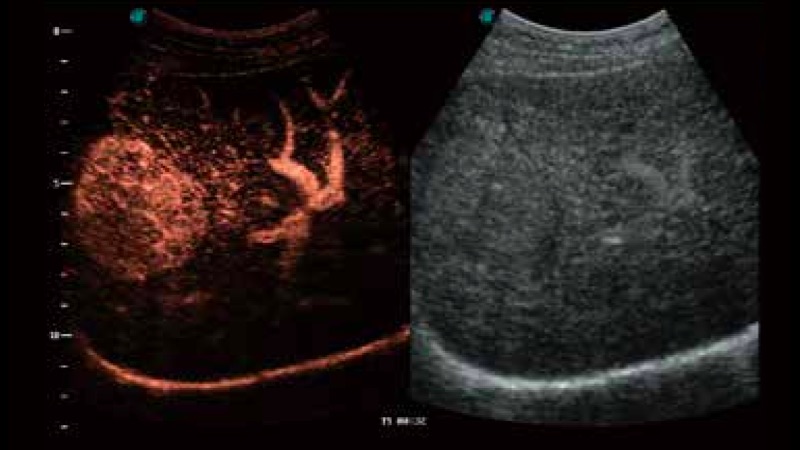

临床图像

造影成像

造影成像功能和定量分析工具包使医生能够更好的评估血流灌注情况。独特的动态声压控技术有效控制造影剂的声压,保证更长的造影剂持续时间,更好的观察病变灌注的延迟相位。